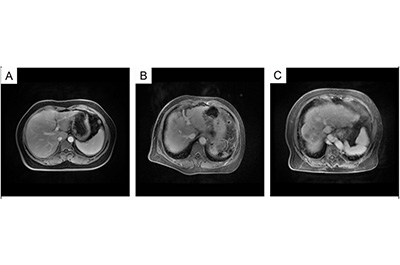

此外,研究还观察到,CHC患者的肝脏MRI表现接近健康肝脏,而HCV诱导的肝硬化患者肝脏体积缩小、轮廓改变,HCV相关HCC患者肝脏表面不平、信号不均且有异常信号。从外泌体的超微结构来看,不同疾病患者的外泌体均呈圆形或椭圆形,直径约30-100nm,无法区分。